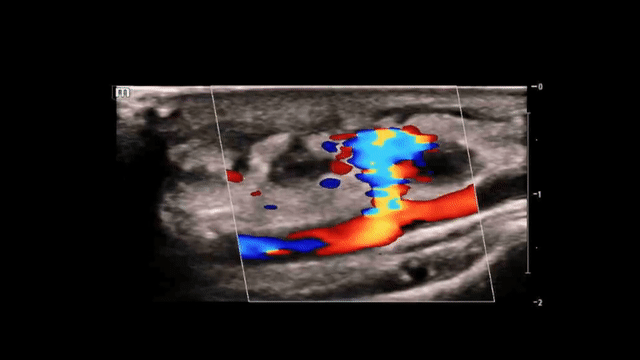

Using color doppler, there was evidence of blood flow within the hypoechoic structure, with a clear connection to the radial artery.

(Short-axis view of the right wrist with color doppler)

(Long-axis views of the right wrist with color doppler, bottom image shows the classic “yin-yang” sign which will be discussed below)

• Hypoechoic sac with a narrow neck extending from the radial artery

• “Yin-Yang” sign (turbulent bidirectional blood flow)

Here is a classic image of the characteristic “yin-yang” sign: